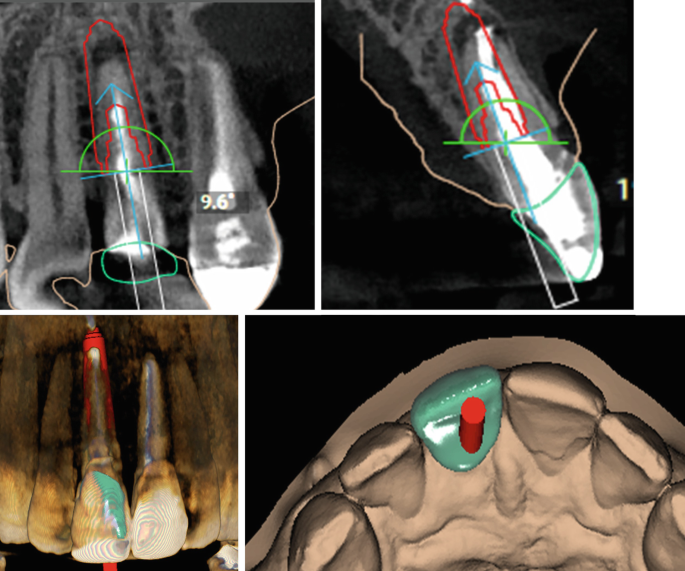

Advances In Dental Implantology